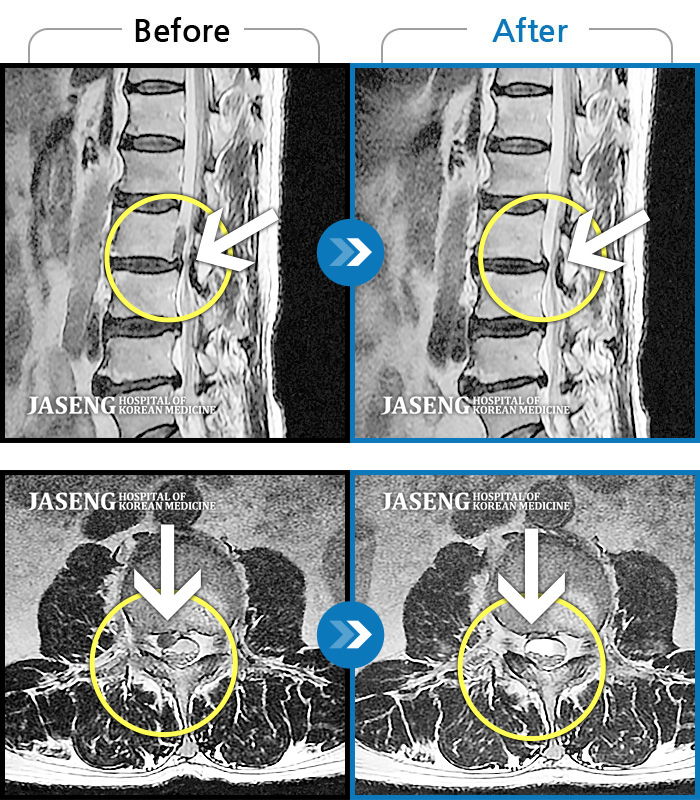

허리디스크

일산 · 배영현 원장

처음 내원 시 허리, 엉덩이가 많이 아프고, 좌측 다리에 힘이 빠지며 감각이 둔하여 정상적인 보행이 힘든 상태셨습니다.

촬영시기

2022.05.24 ~ 2023.05.13

2023.06.01